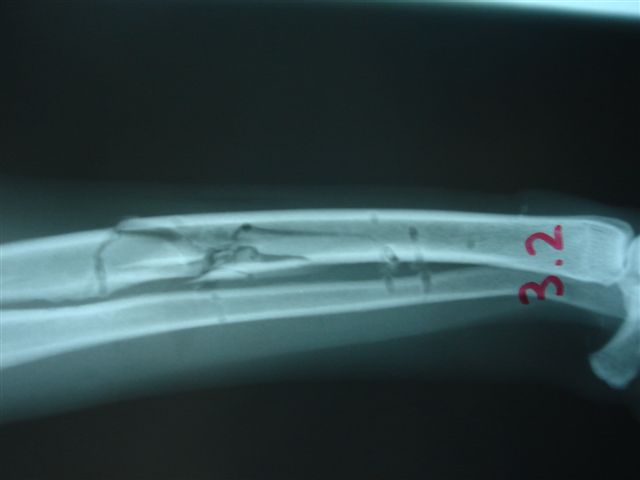

Fijación Externa en IVOT

Fijación Externa

IX CURSO BASICO DE FIJACION EXTERNA.

Casos prácticos alumnos.